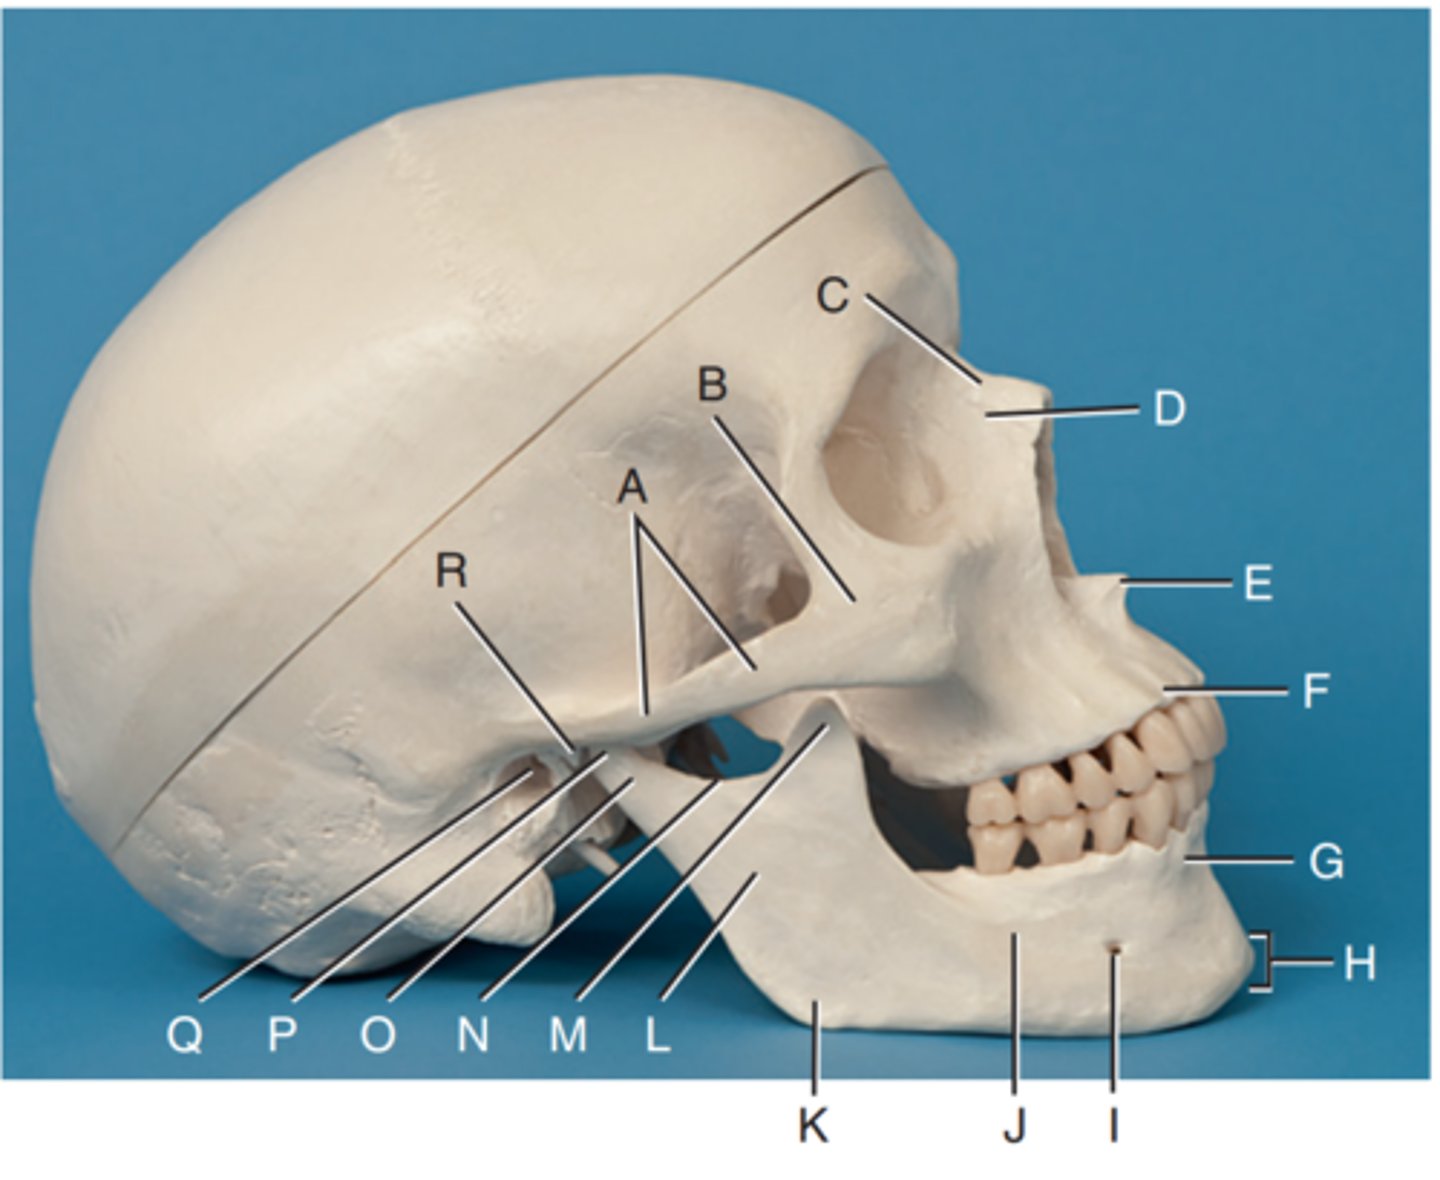

Zygomatic arch

Label A

Right zygomatic bone

Label B

Right nasal bone

Label C

Frontal process of right maxilla

Label D

Anterior nasal spine

Label E

Alveolar process of maxilla

Label F

Alveolar process of mandible

Label G

Mentum or mental protuberance

Label H

Mental foramen

Label I

Body of mandible

Label J

Angle (gonion)

Label K

Ramus of mandible

Label L

Coronoid process

Label M

Mandibular notch

Label N

Neck of mandibular condyle

Label o

Condyle or head of mandible

Label P

EAM

Label Q

TM fossa of temporal bone

Label R

Greater wings of sphenoid

Label S

Lesser wings of sphenoid with anterior clinoid processes

Label T

Ethmoid sinuses between orbits

Label U

Body of maxilla containing maxillary sunuses

Label V